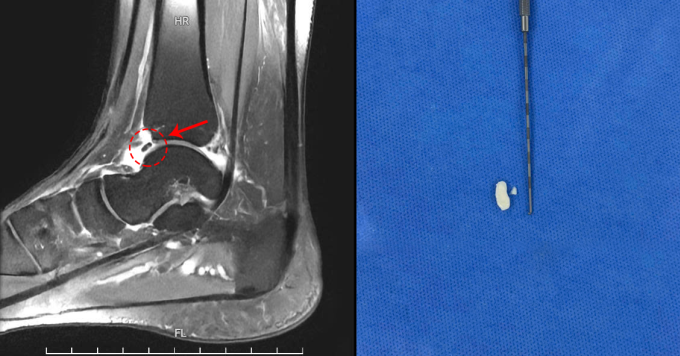

BS.CKII Trần Tuấn Anh, Khoa Chấn thương Chỉnh hình, Bệnh viện Đa khoa Tâm Anh Hà Nội, cho biết kết quả siêu âm, chụp X-quang và cộng hưởng từ MRI, ghi nhận mảnh xương di động kích thước 3,6×1,6 mm gây hội chứng chèn ép khớp cổ chân kèm viêm bao hoạt dịch khớp cổ chân.

Mảnh xương, sụn rời trong khớp người bệnh trên phim chụp MRI (trái) và sau khi được phẫu thuật loại bỏ (phải). Ảnh: Bệnh viện Đa khoa Tâm Anh

Bác sĩ Tuấn Anh phẫu thuật nội soi cho chị Hương để lấy mảnh xương và sụn ra ngoài. Bác sĩ ứng dụng phẫu thuật nội soi khớp cổ chân với hai đường mổ nhỏ 0,5 cm phía trước trong và trước ngoài khớp cổ chân để đưa trocar, camera vào khớp, đánh giá các tổn thương. Bác sĩ cắt lọc bao hoạt dịch viêm, lấy mảnh xương và sụn ra ngoài, kiểm tra không còn dị vật trong khớp sau đó đóng vết mổ và băng ép.